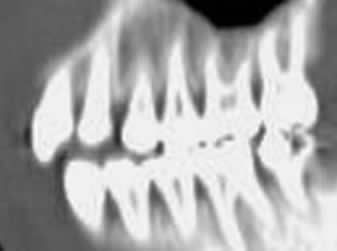

Fig 2. Dentición permanente.

TAC reconstrucción sagital. Dientes en contacto con su opuesto, con lo que termina la migración.